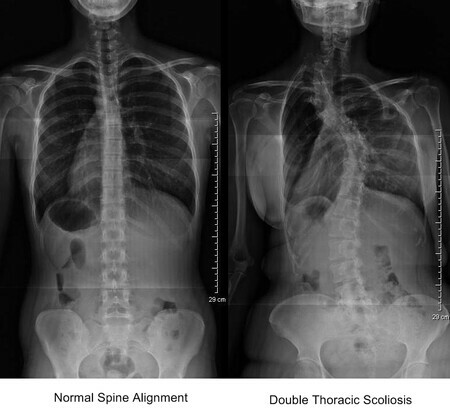

Example: If your left hip is higher than your right hip, your spine will start to move right. It needs to quickly move back left in order for the spine to stay level and for you to continue standing. Without this adjustment, gravity will pull your torso and cause you to fall to your right side. This high hip causes a cascade of compensation up your spine which will result in a curved spine.

The normal curvature of the spine is under 10 degrees. Some people have 5-6 degrees of curvature and others have 40. When correcting those with an irregular spinal curvature, all the vertebra, ligaments (mainly 4) that hold your spine together, along with the muscle that secures and moves your torso, need to be taken into account.